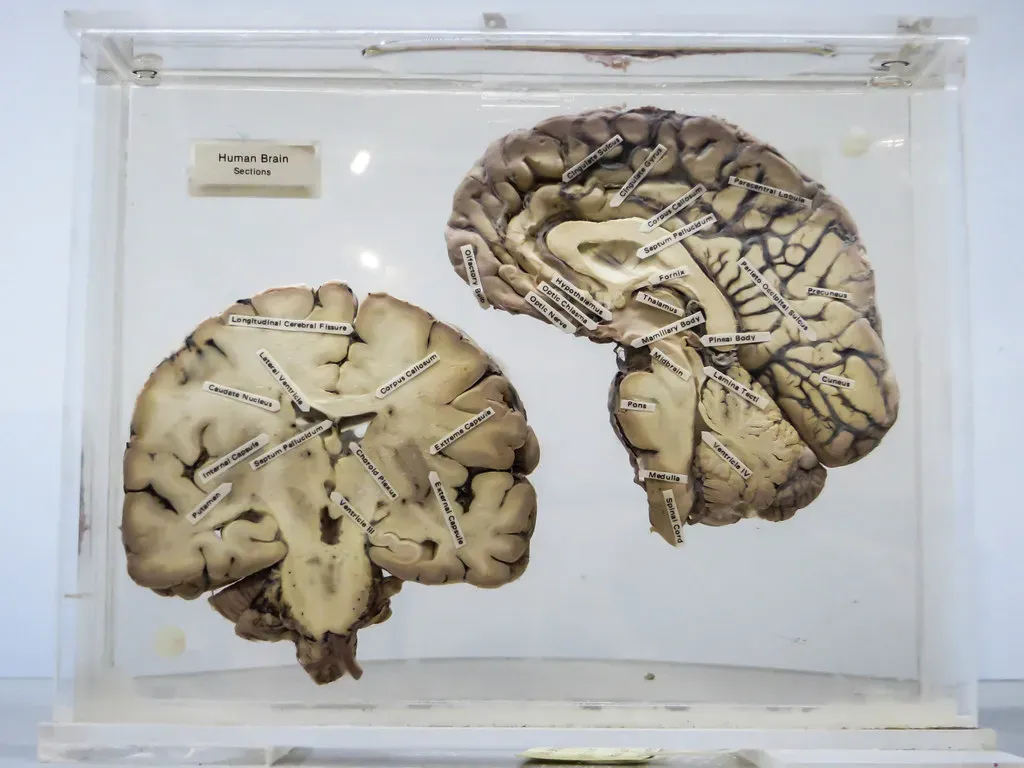

What Each Single Synapse Actually Does

Here’s something most people don’t realize. When you picture a synapse, you might imagine a simple on-off switch. That’s completely wrong. One synapse, by itself, is more like a microprocessor – with both memory-storage and information-processing elements – than a mere on/off switch. In fact, one synapse may contain on the order of 1,000 molecular-scale switches. That’s an enormous amount of computing power packed into something you couldn’t see with the naked eye.

Synapses are the spaces over which neurons send and receive electrical and chemical signals. The brain’s magical ability to learn, and to recall information already learned, depends on synapses. Researchers at the Max Planck Institute have gone even deeper into this. The research team identified more than 1,800 unique synapse type-enriched proteins, revealing a stunning diversity of molecules that underlie synaptic connections. So not only are there an almost incomprehensible number of synapses – each one is itself a universe of molecular complexity.